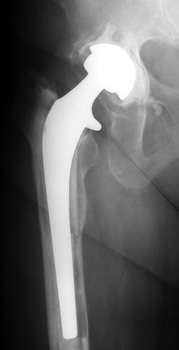

LooseningAs pain and disability due to loosening become severe enough to require revision arthroplasty, abnormalities in the binding of the cement to the bone or prosthesis are almost always visible radiographically. Radiographic abnormalities include:

No prior studies available. Abnormally widened interfaces surrounding entire cement mantle of femoral component, consistent with loosening.

No prior studies available. Abnormally widened interfaces about femoral component at Gruen zones 1, 6, and 7. Osteolysis at Gruen zone 5 with marked thinning of femoral cortex placing patient at risk for pathologic fracture.

SUBSIDENCE - loose femoral prosthesis with interface widening,

osteolysis Gruen zone 6, cement fracture left femoral component

and osteolysis, with femoral component in valgus.